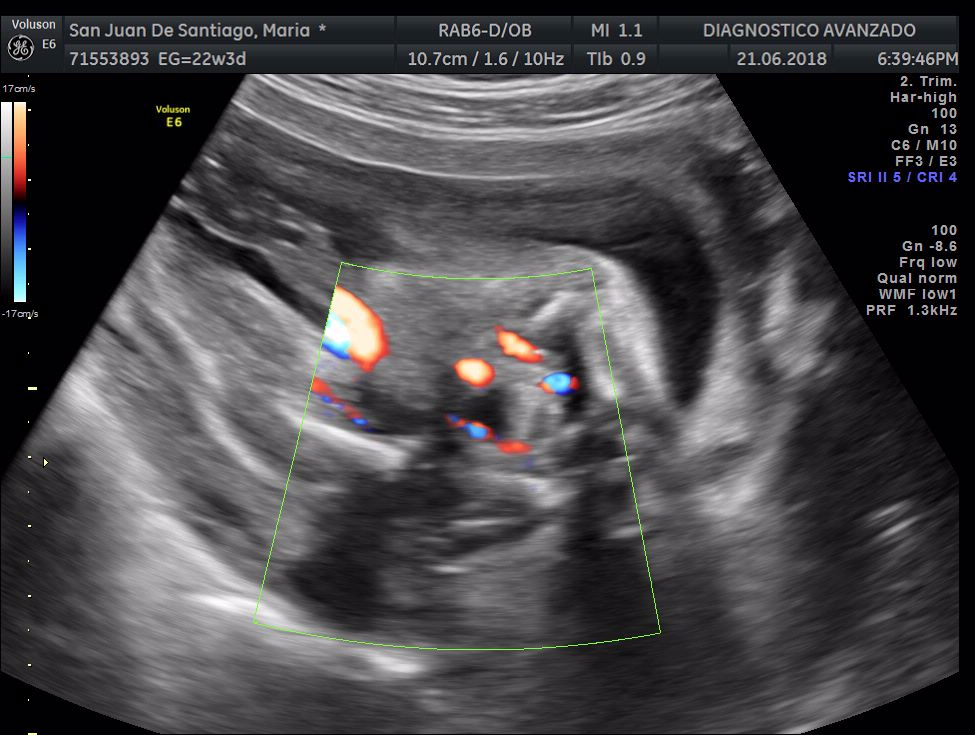

¡Hola a todos! Hoy hemos ido a hacer la tradicional ecografía 3D de la niña, os dejamos todo el material (aunque es un poco demasiado).